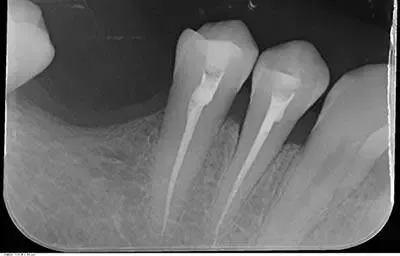

Se il dente è dolente è possibile effettuare un trattamento canalare, definita anche devitalizzazione, un trattamento che rende totalmente asintomatico l’elemento dentale. Successivamente è sempre possibile effettuare una otturazione, ricostruzione o corona.

Anche denti già devitalizzati non curati correttamente e che presentano delle lesioni periapicali (granulomi) si possono recuperare con idonee terapie canalari definiti ritrattamenti dentali.